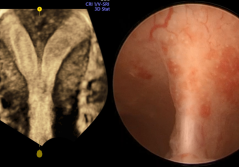

Frau Dr. med. Efthymia Konstantinidou hat richtig getippt, bravo! Ja, ein APVS ist eine seltene Herzfehlbil-dung, charakterisiert durch eine fehlende (oder dysplastische) Pulmonalklappe, ein Out-let-Ventrikelseptumdefekt (VSD) und eine darüber reitende ... PDF DokumentIm Bild: Extrauteringravidität in rudimentärem Uterushorn (4Ua)

28-jährige Patientin mit notfallmässiger Hospitalisation in der 11. SSW bei akut aufgetretenen Unterbauchschmerzen links, einem bHCG-Wert von 30 000 mIU/ml bei ansonsten unauffälligen Laboruntersuchungen, kein aktueller Kinderwunsch. PDF DokumentIm Dialog: Gynäkologie und Glauben im Dialog!